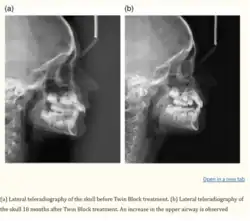

The size of the condyle, distance between the two condyles, and the length of the mandible increased. The twin block appliance enabled the growth of the condyle in a backwards and upwards direction. Based on cephalometric analysis, as given in Figure 21, the angle of SNB (the position of the mandible to the base of the skull) increased, and the angle of SNA (the position of the maxilla to the base of the skull) and ANB (anteroposterior relationship between the maxilla and mandible) decreased thus reducing the Class II skeletal malocclusion.[24]

Skeletal changes

Twin Block treatment was found to contribute to Class II correction, with 49.88% of skeletal changes. The cephalometric landmarks of the facial skeleton and skull base have been shown in Figure 22. Males exhibit greater skeletal changes compared to females.[27]

Effects on the maxilla

- SNA angle exhibits minimal reduction after functional treatment.[27]

- Indicate that the forward growth of maxilla is restricted and a headgear effect is produced.[28]

Effects on the mandible

- There is an increase in the mandibular length.[27]

- There is a reduction in the articular angle (S-Ar-Go), indicating mandibular forward repositioning, leading to opening of the bite to improve the deep bite.[27]

Maxillo-mandibular changes

- Increased length of mandible and restricted maxillary growth in sagittal plane lead to an increase in SNB angle.[27]

- This increased SNB angle results in improvement of ANB angle.[27]

- Reduction in ANB angle indicates that the anteroposterior relationship between maxilla and mandible is improved.[27]

- There is also a reduction in the distance from nasion perpendicular to the pogonion point (N perpendicular to point Pg).[27]

- This depicts that the change in mandible position can lead to the change in maxillomandibular relationship.[27]

Singh et al. found that the Twin Block appliance can improve airway function by increasing the posterior airway space. This advancement in the mandible can be particularly beneficial for patients suffering from obstructive sleep apnea (OSA) or other breathing difficulties, as it helps to reduce airway obstruction during sleep. This makes the appliance useful not only for orthodontic correction but also for improving overall health and breathing.[25]